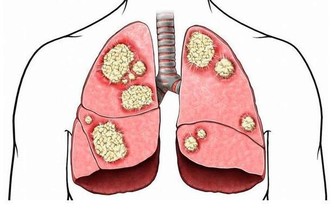

牙齦有話說 除了食道外,牙齦的意見也很大:食物太燙,牙齦會被燙傷。可還來不及修復,又一批燙食進口了。長期下去,牙齦就會用潰傷來抗議了。長期的燙食還會引起牙本質過敏,引發過敏性牙痛。 癌症找上門 大家都有不小心吃了燙食的經歷,不想吐出來時通常會讓食物在口腔中快速倒幾下。而熱愛燙食的人每頓飯都是如此。這會讓食物在口腔還沒充分,就進胃了,加重了胃的負擔,影響了食物的消化和吸收。而這樣燙食也會讓胃潰瘍啦。 可食道也不願意整天破破爛爛的,只好不停地增生修復。在這樣一次次的傷害——增生——修復過程中,增生的細胞中會漸漸產出一些杯分子,也就是型態、功能不正常的「異形性」細胞。當這些不正常的細胞多了,惡變也就發生了。食管黏膜上皮的表面就會出癌症,隨著癌組織的不斷擴大,癌腫瘤侵占食道的空間也越來越多,很多患者都是感到吞咽困難或有異物感才到醫院就診,這時候一檢查,得!食道腫瘤,做手術吧!